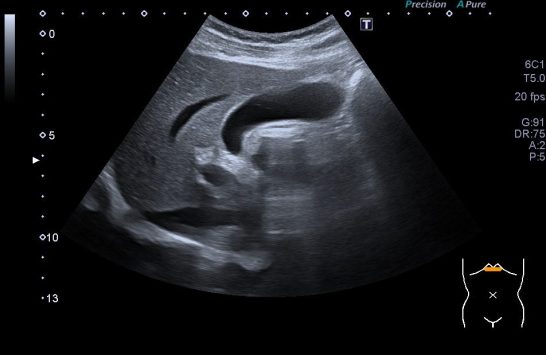

De la imagen 1 a 3 ves un hígado afectado por una cirrosis hepática. En ella vas a ver un tejido anormalmente heterogéneo, parcheado en ocasiones, como con «grumos», a veces muy pequeños, otras veces más grandes. Son los nódulos de regeneración. Cuando las células del tejido hepático se mueren son sustituidas por tejido cicatricial. Puedes ver el borde hepático abombado. Los cambios en la ecogenicidad son variados, te he decimos algunos, no me interesa contarte esto, me interesa que compares la imagen 1,2 y 3 con la imagen 4 y veas patología y normalidad del parénquima hepático. Muchas veces una imagen vale más que mil palabras, lo sé…